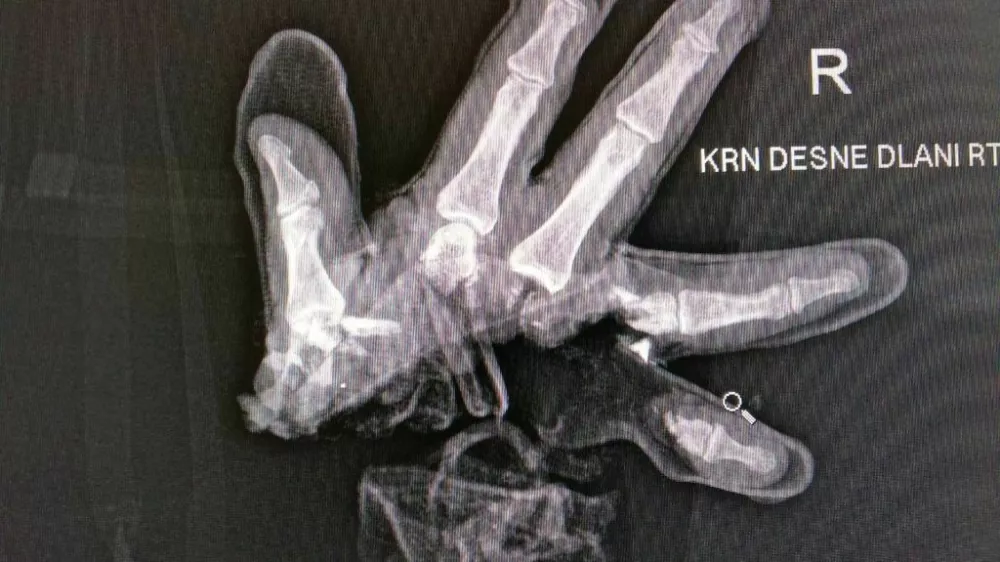

Ljubljanski policisti so sporočili, da se je včeraj ponoči na območju policijske postaje Moste s pirotehniko hudo poškodoval 20-letni moški. Ima hude poškodbe roke, njegovo življenje po prvih informacijah ni ogroženo.